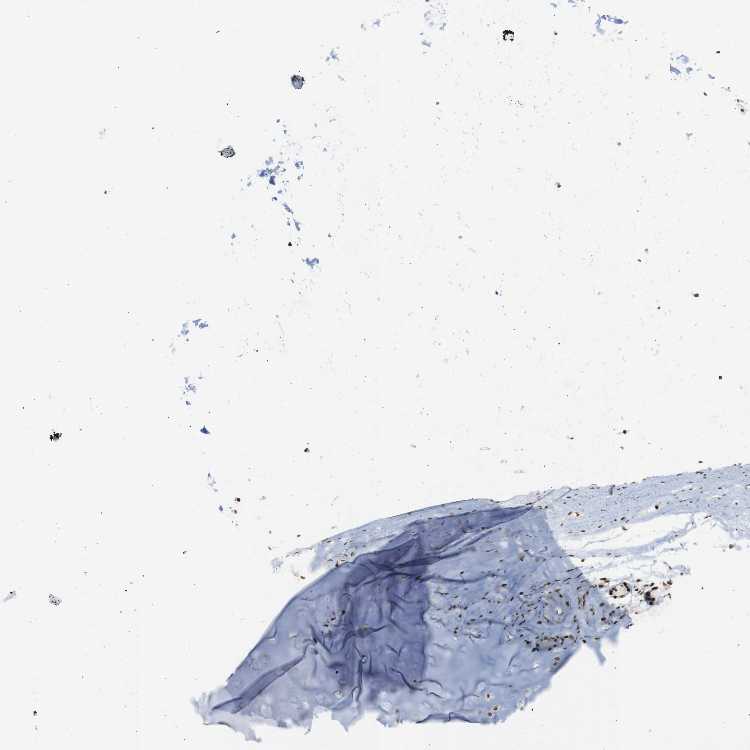

SOFT TISSUE 2 - Antibody stainingi

Antibody staining in the annotated cell types in the current human tissue is reported as not detected, low, medium, or high, based on conventional immunohistochemistry profiling in selected tissues. This score is based on the combination of the staining intensity and fraction of stained cells.

Each image is clickable and will lead to virtual microscopy that enables deeper exploration of all samples and also displays staining intensity scores, fraction scores and subcellular localization as well as patient and tissue information for each sample.

Antibody HPA067966Antibody CAB012432

Fibroblasts Not detectedHigh

Peripheral nerve Not detectedHigh